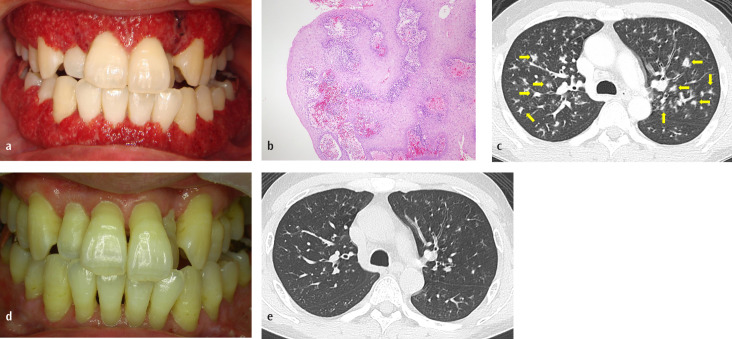

Strawberry Gingivitis: Rare Early Manifestation of Relapsing Granulomatosis with Polyangiitis

草莓牙龈炎:复发性肉芽肿病合并多血管炎的罕见早期表现。